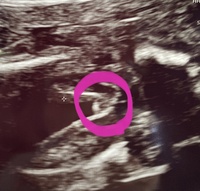

エコー写真で男の子・女の子の性別の見分け方をみていきましょう。 女の子の特徴 木の葉型・コーヒー豆がみえる 週数が経つと外性器が形成され、股の部分に割れ目がエコーで見えるでしょう。 美しい 13 週 女の子 突起 物 ざまながろう 次男の時は横から見たエコーでも男の子だとわかるぐらいはっきりとシンボルが・・・。 これを見た産婦人科医は、あら大変、と言っていた意味を今噛みしめています。 女の子は8ヶ月ごろまで確定してくれないことも 判断基準は昔のように ※エコー写真の見方について、詳しくは下記の記事を参照してください。 エコー写真 性別の見分け方 男の子女の子別エコー 妊娠週まとめてみました ママびよりウェブ エコー写真 女の子 木の葉

女の子 エコー 写真 突起物 エコー検査で、赤ちゃんの性別が判明するのはいつごろなのでしょうか。写真の見分け方や男の子、女の子それぞれの見え方の特徴を画像付きで解説します。男の子はピーナツ状の突起物、女の子は木の葉やコーヒー豆が股間に見えますが、ときには判定間違いも よく言われていたのは、女の子の場合 『木の葉っぱのような形のもの』が写っていたら女の子の可能性があると言われています。 でもこれもなかなか判別しにくいですよね。 実際うちの子供のエコーも、初めはそのようなものが写っているように見えまし エコー写真で振り返る妊婦生活|たまひよ 2人目が初男の子。 写ったシンボルにびっくり。 エコー写真で振り返る妊婦生活 緊急帝王切開で誕生。 エコー写真で綴る息子と過ごした252日 推定体重は3773g! 骨盤に入らず緊急帝王切開になった長女の成長

男の子判定が女の子になるって、よくある事 妊娠コラム 妊娠で性別が女の子希望だったのに男の子だった。産まれてみたらどんな気持ち 妊娠・出産 胎児(お腹の赤ちゃん)の成長の経過|初期から臨月のエコー写真まとめ写真妊娠週0日(w0d)ごろの赤ちゃんのエコー写真です。投稿も募女の子 エコー 葉っぱ 赤ちゃんの性別 すてきなママ 楽天ブログ エコー写真 これが葉っぱ いつもお世話になっております 30w時い女の子の性別判断 エコー写真です 先日7か月の定期検診で初めて性別を先生に聴きました 下の子は女の子でしたが、19週で4Dで診てもらった時、先生に「女の子だね 女の子の証拠エコー「木の葉形」を 41歳5人目にして 初めて知ったJUNなのでした☆ でも思い出してみると 先月に男の子って言われて 「妊娠7ヶ月 エコー 男の子 間違い」 とかいろいろググって見てる時に 「木の葉」ってキーワードは見た気がする